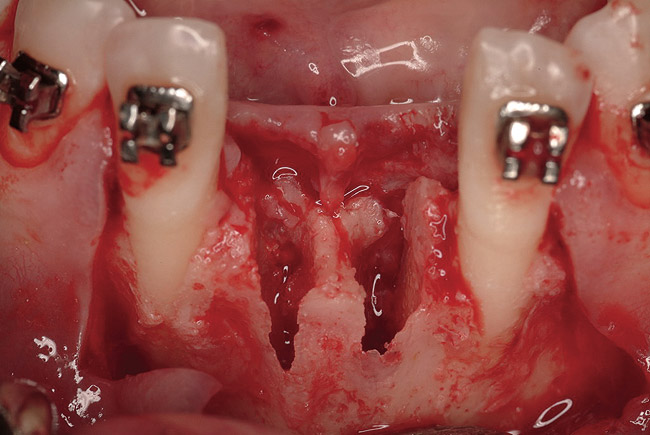

Disadvantages to this technique include time necessary for mesh shaping, manipulation, and fixation. But perhaps the greatest shortcoming of titanium mesh is the necessity of its removal. This requires wide flap reflection and frequently sharp dissection (Figure 1). Often, a dense, soft-tissue layer is found over the mesh, referred to by Boyne10 as a “pseudo-periosteum.” This tenacious soft tissue is tightly bound to the mesh and underlying bone, requiring sharp dissection and elevation of the material. This adds significant operative time to the procedure. This type of soft tissue is shown in Figure 2; the mesh removed at the time of implant placement still has the tissue attached following sharp dissection and elevation. The wide flap reflection and time needed to remove the mesh increases morbidity associated with the second surgical procedure, primarily intended for implant placement. The evolution of this technique has led to the development of a rigid but resorbable mesh. The challenge for clinicians and researchers is to find a resorbable mesh capable of space maintenance comparable to titanium mesh, yet composed of a material that is biocompatible and does not compromise regenerative outcomes.

Figure 1  Note wide flap reflection necessary for titanium mesh removal and implant placement. The apical extent of the flap is necessary not only to remove the mesh but also two fixation screws that need to be placed at a safe distance from the apices of the adjacent teeth.

Figure 1